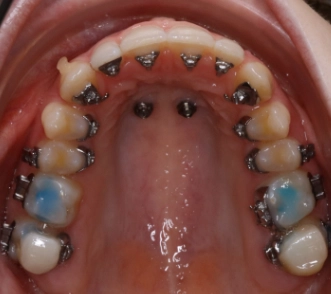

digitale Pin Planung

2 Gaumenpins